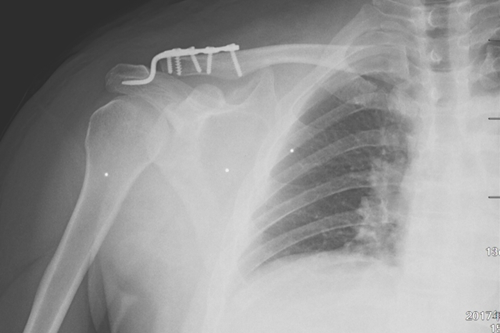

一名50岁的男性患者,因不慎摔伤致右肩关节肿痛,并伴活动受限4天后来附院求治。入院查体发现患者右肩部肿胀明显,右锁骨远端隆起畸形,局部明显按压出现疼痛,肩部外展活动受限,进行X线检查显示“右肩锁关节脱位”。骨三科医师团队根据患者病情,进行充分商讨,确定了手术治疗方案,决定为患者实施“右肩锁关脱位复位带袢钢板内固定术”。由副主任医师蒋宇平主刀,骨三科手术团队在患者锁骨上方及喙突处各取2cm手术切口,将肩锁关节复位后,使用瞄准器由喙突基底部向锁骨远端建立骨性隧道,最后将带袢钢板由骨道穿出后固定,术中出血仅10ml左右。

术前DR